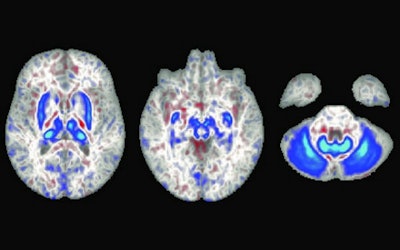

The researchers found individuals with the homozygote for p.C282Y mutation had lower T2-weighted and T2* intensities in the brain regions related to motor control, a finding that is consistent with higher iron deposition in these areas. The imaging associations they discovered are consistent with a class of disorders called neurodegeneration with brain iron accumulation (NBIA), a condition in which genetic mutations lead to iron buildup in the basal ganglia, which in turn can lead to movement disorders.

"This iron deposition is believed to lead to oxidative damage of these brain regions, impairing their function and resulting in movement deficits," Loughnan et al wrote. "Hemochromatosis has traditionally not been included as a cause of NBIA."